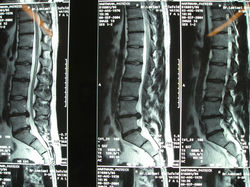

![]() Aorta abdominalisKontrastmitteldarstellung der Bauchschlagader und der Nierengefäße | ![]() Wirbelbruch | ![]() MRT: Prolaps L4/5Bandscheibenvorfall zwischen 4./5. Lendenwirbel | ![]() NMR LWS Prolaps QuerschnittMRT-Querschnitt; Bandscheibenvorfall der Lendenwirbelsäule mit Nervenkompression |